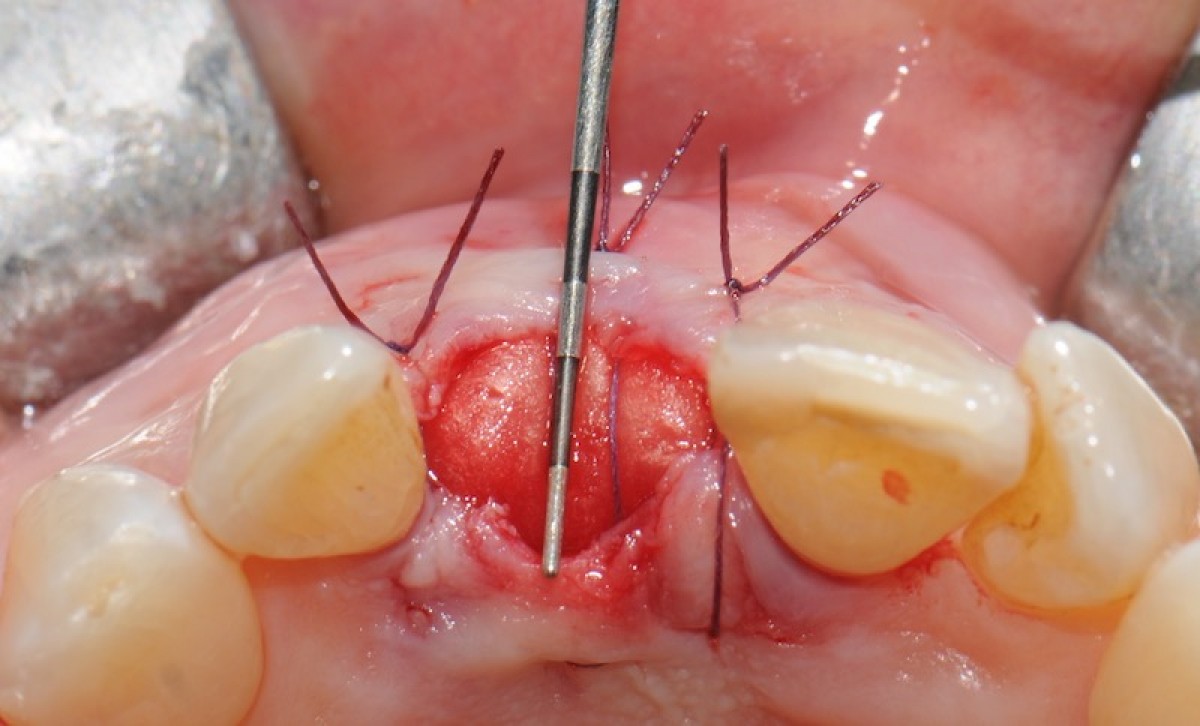

The objective of this prospective cohort study is to test the performance of a new xenogenic collagen matrix as a socket sealing material, to allow second-intention healing of post-extractive sockets filled with a xenogenic bone substitute or with an immediate submerged implant.

10 patients were recruited, presenting a single-rooted tooth scheduled for extraction. After atraumatic tooth removal, the post-extractive alveolus received either a socket preservation procedure or an immediate submerged implant. In both cases, the gingival margins of the alveolus were sealed with a xenogenic collagen matrix (Mucoderm, Botiss Dental, Zossen, Germany). The following parameters were evaluated:

• exposed surface of the matrix at the end of surgery (T0);

• soft tissue healing at 1, 4, 6, and 8 weeks from surgery (T1-4);

• histological aspect of gingiva samples, harvested 20 weeks after surgery (T5);

• aesthetic performance provided by the socket sealing material (T4).

• the mean post-operative exposure area of the matrix was 26.25 mm2 (14.2 to 38.84 mm2 );

• 8 weeks after surgery, full wound closure was achieved in 9 out of 10 sites with healthy keratinized tissue;